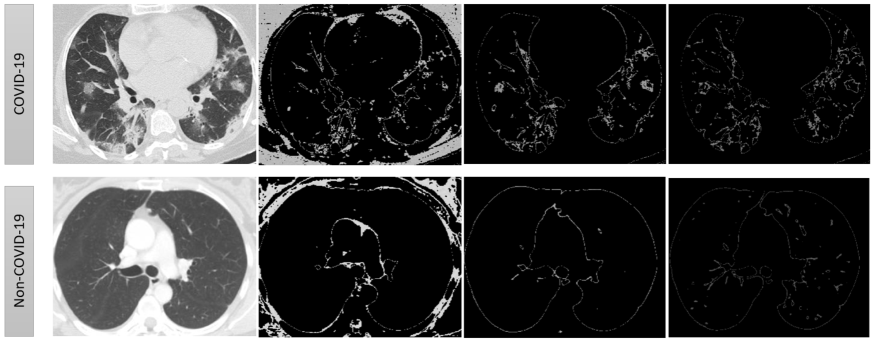

3.1.2 PDs: Capturing the Visible

This filtered complex, defined in the previous section, is able to capture the key features of a CT-scan, like, peaks, variations in intensity, etc. Connected components and appearance of loops at different intensity levels are captured in the PD’s of , and respectively (see Fig. 10). The PDs of and for the images in Fig. 10 are given in Fig. 12. It is evident that the difference in their visual appearance is captured by these PDs.

Lower Star Filtration (LSF) captures key features about variation in intensities in an image. Local minimum and saddle points, in the intensity plot, are vital shape features (see Fig 11). These features are recorded using LSF. The birth time of a point in this PD is local minimum and death time is saddle point.

To record these changes, we construct a simplicial complex, say , in the following way. Each pixel is taken as a vertex, and there is an edge from one vertex to its neighbouring 8 (or less in case its an edge vertex) vertices. This allow us to construct the filtration where here is the pixel value of the vertex . Only the zero-dimensional PD is essential for our model development. The Fig.12 shows a major difference between the PDs associated to LSF of a COVID-19 and a non-COVID-19 CT-scan image.